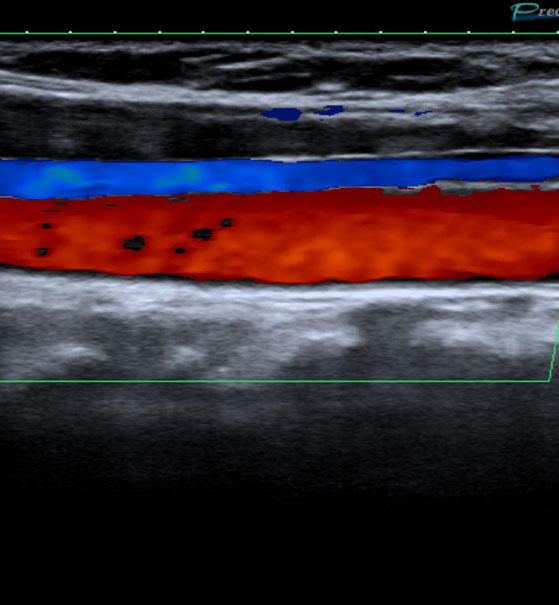

Farbdopplersonographie

Die Farbdopplersonographie ist eine zuverlässige Methode zur Beurteilung von Arterien und Venen. Die Farbdopplersonographie kann einerseits Veränderungen der Gefäßwände (z.B. arteriosklerotische Plaques) und dadurch resultierende Engstellen (Stenosen) nachweisen, andererseits durch Blutflussgeschwindigkeitsmessungen den Schweregrad der Stenosen beurteilen. Risikofaktoren für Arteriosklerose und damit für Schlaganfall und Herzinfarkt sind z.B. erhöhte Blutfettwerte, hoher Blutdruck (Hypertonus), Nikotinkonsum.